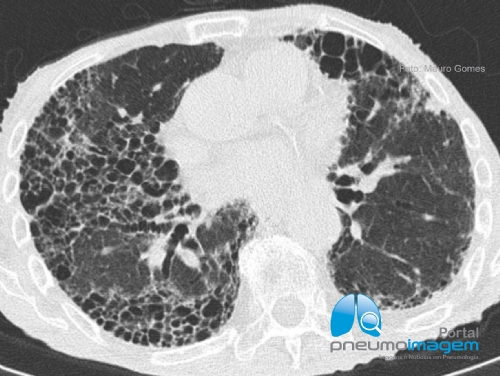

Foi aprovado no Brasil no final do mês de junho o uso do nintedanibe para o tratamento das doenças pulmonares intersticiais (DPIs) crônicas com fenótipo fibrosante progressivo.

Isso significa que os pacientes com doenças que apresentam caracteristicamente fibrose pulmonar progressiva, piora da função pulmonar, dos sintomas e da qualidade de vida, com mortalidade precoce podem agora utilizar a droga para o seu tratamento, independente do diagnóstico de Fibrose Pulmonar Idiopática (FPI).